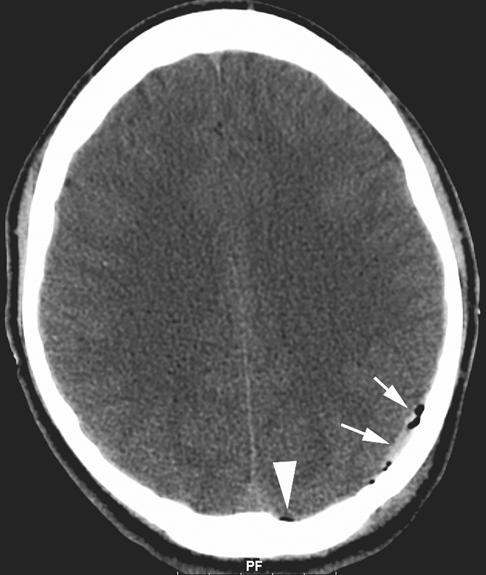

3/ máu tụ dưới màng cứng

Máu tụ dưới màng cứng là tình trạng máu tích tụ trong khoang giữa màng cứng và màng nhện [3]. Đây cũng là một khoang ảo, nhưng khi có chảy máu, máu sẽ lan rộng dọc theo bề mặt não thay vì tạo khối khu trú.

Nguyên nhân thường gặp là do rách các tĩnh mạch cầu nối – các tĩnh mạch dẫn máu từ não về xoang tĩnh mạch màng cứng. Khi có chấn thương, đặc biệt là lực gia tốc – giảm tốc đột ngột, các tĩnh mạch này dễ bị kéo căng và đứt. Do nguồn chảy máu là tĩnh mạch nên áp lực thấp và tốc độ chảy chậm hơn so với động mạch, khiến khối máu tụ hình thành từ từ [4]. Vì vậy, bệnh thường diễn tiến âm thầm và dễ bị bỏ sót. Tình trạng này đặc biệt hay gặp ở người cao tuổi do hiện tượng teo não làm tăng khoảng cách giữa não và màng cứng, khiến các tĩnh mạch cầu nối dễ bị kéo căng và tổn thương, hoặc ở những bệnh nhân có tiền sử chấn thương nhẹ nhưng không được chú ý.

Về lâm sàng, máu tụ dưới màng cứng không có “khoảng tỉnh” điển hình như máu tụ ngoài màng cứng mà các triệu chứng thường xuất hiện một cách từ từ và tiến triển dần theo thời gian. Bệnh nhân có thể biểu hiện đau đầu kéo dài, lú lẫn, giảm trí nhớ, thay đổi tính cách hoặc hành vi, và dần dần xuất hiện các dấu thần kinh khu trú như yếu hoặc liệt nửa người. Khi khối máu tụ lớn lên và gây tăng áp lực nội sọ, bệnh nhân có thể giảm tri giác, thậm chí hôn mê [6]. Trong thể cấp tính, triệu chứng có thể xuất hiện sớm và rầm rộ hơn, tuy nhiên nhìn chung vẫn chậm hơn và ít điển hình hơn so với máu tụ ngoài màng cứng.

Nguồn: Ly, J. Q., Sanders, T. G., Smirniotopoulos, J., & Folio, L. Subdural hematoma. ResearchGate.